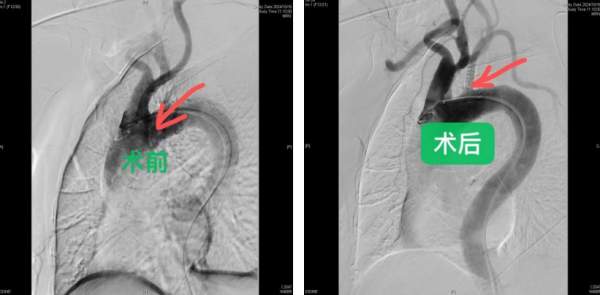

图片说明:术前:左锁骨下动脉未见显影,延迟造影见左锁骨下动脉经左椎动脉供血,也就是“盗血”;术后:左锁骨下动脉闭塞段经过球囊扩张及支架植入,可以看到左锁骨下动脉造影良好,血流通畅。

“患者在心血管内科接受了颈动脉与锁骨下动脉的彩超检查,检查结果明确显示其左锁骨下动脉存在闭塞现象,并伴随有左锁骨下动脉盗血综合征。基于这一诊断结果,经过多学科会诊,患者被转至外周血管介入科进一步治疗。”赵扬程介绍。随后,赵扬程主任及其团队对患者的病情进行了全面评估,并决定采用介入手术进行治疗。在DSA数字减影血管造影下,医生成功将导丝通过患者左锁骨下动脉的闭塞段,并实施了球囊扩张和覆膜支架植入手术,成功开通了闭塞的左锁骨下动脉。